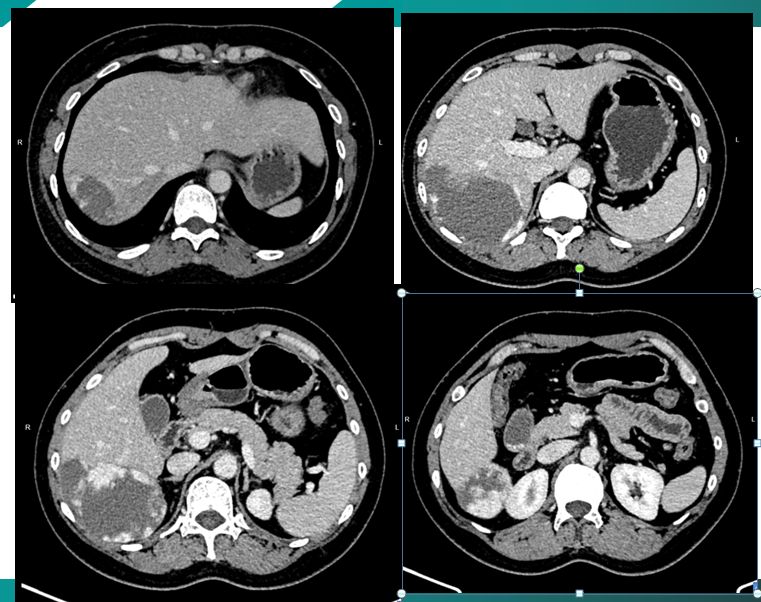

新年首日,科室接到紧急诊疗需求,患者因肝占位性病变急需手术干预,若延误治疗,将严重威胁生命健康。考虑到患者病情复杂、对创伤耐受度较低,肝胆胰外科许其威主任牵头组织团队进行多学科会诊(MDT),参与讨论人员温江涛副主任医师、韩永锋副主任医师、毛延兆主治医师、兰军良副主任医师、李海锋主治医师、段磊主治医师、影像医学科高晓玲主任、肿瘤科李晖主任,根据患者影像学检查、肝功能指标及全身基础状况,反复研判手术方案,最终确定采用腹腔镜肝叶切除术。该术式具备创伤较小、出血较少、术后恢复较快等优势,能一定程度降低手术对患者身体的损伤,更符合患者希望术后更快康复的需求,同时对手术团队的操作精准度、配合默契度提出极高要求。

手术于上午9:30准时开始,手术室吴刚主管护师、冯博洋护师积极准备,麻醉科刘明群副主任医师、王涛住院医师开启麻醉流程,多学科医护人员协同联动,为手术保驾护航。术中,肝胆胰外科团队医师凭借丰富的临床经验,在高清腹腔镜视野下精准定位病灶,熟练操作手术器械,细致分离肝周韧带、结扎相关血管胆管,精准切除病变肝叶,全程动作稳、准、细,有效规避了肝门区重要血管、胆管损伤风险。麻醉医师全程严密监测患者生命体征,及时调整麻醉方案,确保术中生命体征平稳;护理团队默契配合,精准传递手术器械、做好术中护理配合,每一个环节都有条不紊、衔接紧密。